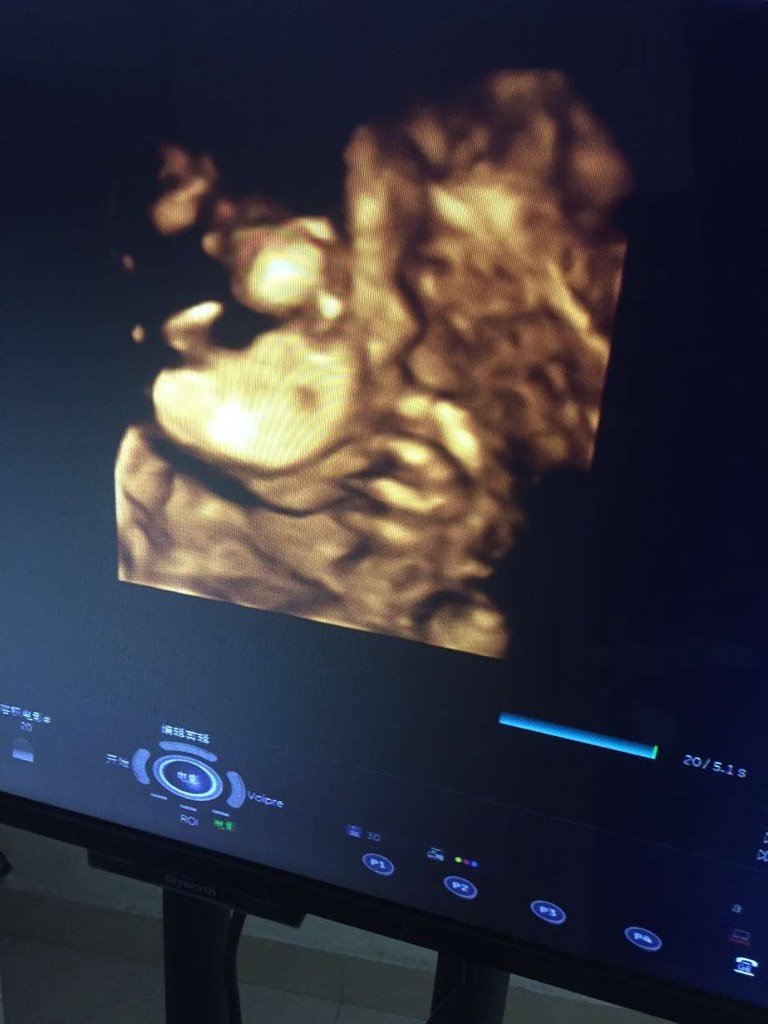

四维彩超可以看到胎儿脸上有胎记嘛,这个脸部的黑点是什么 四维彩超可以看到胎儿脸上有胎记嘛,这个脸部的黑点是什么 点击展开 大美女朋友 2016-10-22 16:59 为您推荐: 其他回答 可能是血管瘤 俊俊的妈妈 2016-10-24 19:03 不可以吧, 天主的恩赐 2016-10-22 23:35 不清楚。。 哎!悔 2016-10-22 23:33 看不到吧, 安安麻麻^ω^ 2016-10-22 23:09 问医生,,, 🐵🐵🐵猴子 2016-10-22 22:21 加载更多 相关问题 四维彩超报告单照片上宝宝额头黑点是胎记么 宝宝眼角下面有一小黑点,是胎记吗?出生时候没有 宝宝额头上的胎记里面有两个黑点'慢慢的变大了